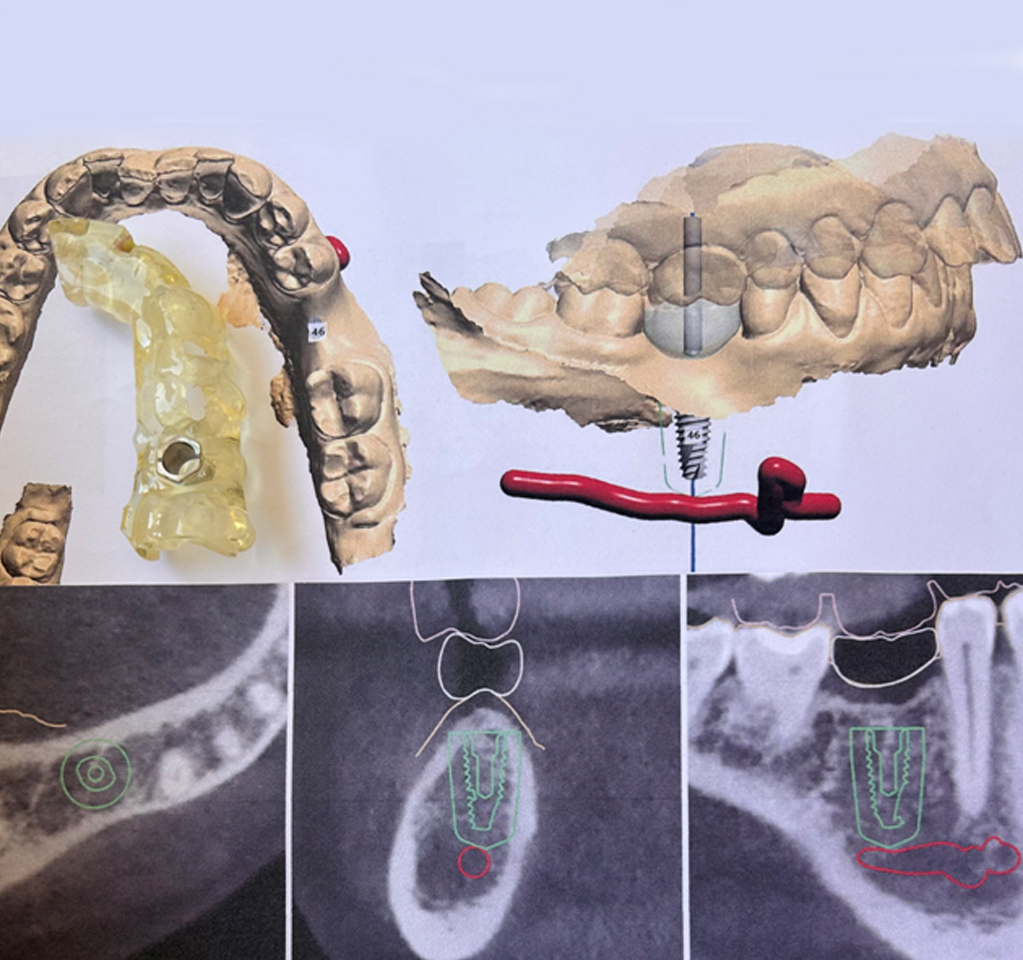

Yπολογιστικά καθοδηγούμενη τοποθέτηση εμφυτεύματος

Σήμερα τοποθετούμε το εμφύτευμα στο σημείο ακριβώς που θέλουμε το καινούργιο δόντι. Πώς το καταφέρνουμε; Με ένα εξειδικευμένο λογισμικό, το οποίο συνδυάζει τα αποτελέσματα της υπολογιστικής τομογραφίας κωνικής δέσμης (=cbct) και της ενδοστοματικής σάρωσης και δημιουργεί ένα μοντέλο στο οποίο μελετάται η βέλτιστη τοποθέτηση του εμφυτεύματος.

Η εξέταση cbct είναι μια στοχευμένη αξονική, η οποία γίνεται σε ακτινολογικό εργαστήριο και λαμβάνουμε τα αποτελέσματα της ηλεκρτονικά. Βάση της μελέτης, κατασκευάζουμε ειδικό χειρουργικό νάρθηκα, ο οποίος μας διασφαλίζει ότι θα τοποθετήσουμε το εμφύτευμα γρήγορα, με υψηλή ακρίβεια και απόλυτη ασφάλεια και άνεση για εσάς.

Τα μηχανήματα και τα οδοντιατρικά υλικά που χρησιμοποιούμε στο ιατρείο για την αποκατάσταση με εμφυτεύματα έχουν ευρωπαϊκά πιστοποιητικά και είναι υψηλής ποιότητας. Θα σας δώσουμε εγγράφως πιστοποιητικό με τα υλικά που χρησιμοποιήσαμε, ώστε να το συμπεριλάβετε στον ιατρικό σας φάκελο.